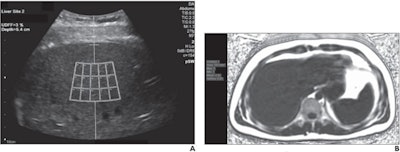

A 23-year-old man with body mass index of 25.1. (A) For ultrasound-derived fat fraction (UDFF) measurement, the operator places crossbar at liver capsule, with sample region of interest fixed 1.5 cm deep from crossbar, to ensure measurement obtained sufficiently deep to liver capsule. Overall UDFF was 3%. (B) Median MRI proton density fat fraction (PDFF) from three acquisitions was 3%, demonstrating agreement. Images courtesy of the American Roentgen Ray Society and the American Journal of Roentgenology.In the study, three MRI PDFF acquisitions were also completed using GE's Ideal IQ whole-liver 3D axial confounder-corrected technique. An image analyst then calculated the PDFF measurements under the supervision of a pediatric radiologist with 10 years of post-training experience, according to the researchers.